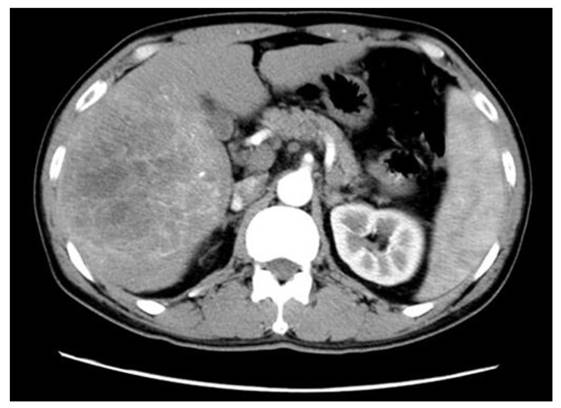

Figure 1

The representative digital subtraction angiography of the patients with HBV-associated ICC who received TACE. All patients who received postoperative TACE were due to early local recurrence of the tumor and all these patients demonstrated relatively abundant blood supply of tumor compared with others that the blood supply to the tumor was less abundant.

TACE was performed by an injection containing a mixture of chemotherapeutic agents with lipiodol followed by embolization with polyvinyl alcohol or gelatin foam up to complete stasis was attained in the tumor-feeding vessels. For the chemotherapeutic agents, epirubicin, cisplatin, and fluorouracil were concurrently used. All patients who received postoperative TACE were due to early recurrence of the tumor (Figure 1).

There were 28 male patients and 14 female patients with a median age of 54 (35-77). Among them, 15 patients (35.7%) were complicated with liver cirrhosis (Table 1). Median size of the primary tumor was 6.5 cm in a range from 2.0 cm to 18.0 cm. A majority of patients (85.7%) possessed single tumor. Nine patients underwent TACE after hepatic resection. Vascular invasion and lymph node metastasis was detected in 16 (38.1%) and 15 (35.7%) patients, respectively. HBsAg was positive in 29 patients (69.0%). Median level for preoperative AFP and CA19-9 was 5.05 (1.25-3000) and 47 (10-8144), respectively. Among 42 cases, only 24 cases were available of preoperative CT scan-related data due to retrospective nature of the study, and 15 patients (62.5%) demonstrated APE (Figure 2).

TACE was performed in 9 patients who demonstrated early recurrence of the tumor; the definition for the early recurrence included both detection of recurrence nodules in CT scans (n = 3) and elevation of serum CA19-9 levels (n = 6) within 12 months after surgery. All patients who received postoperative TACE were seropositive for HBsAg and HBcAb (Table 2). Among them, 4 patients demonstrated elevation of AFP and serum level of CA19-9 elevated in 5 patients. A total of 2 and 3 patients presented with lymph node metastasis and vascular invasion at the time of hepatic resection, respectively. Median size of the tumors was 9 cm (range, 2.5 to 16). All patients who received postoperative TACE demonstrated hepatic APE in preoperative CT scans.